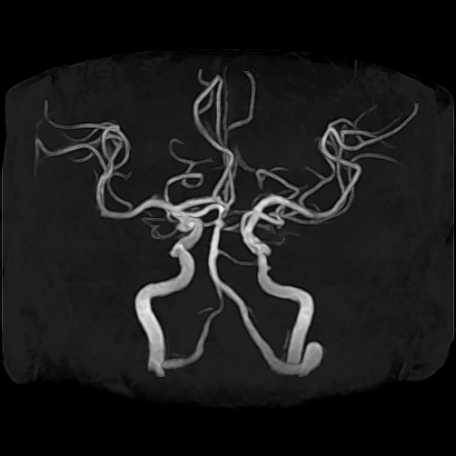

頭部

脳動脈瘤